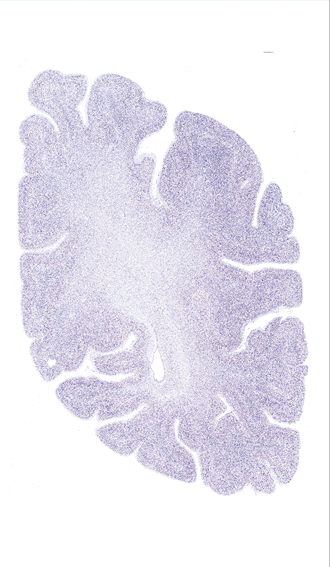

Hi-Resolution Sections · Cells (Nissl Staining) · Virtual Microscopy

Frontal sections (Nissl) from the Atlas Brain:

Microscopy

Slice ID:

r4-0620

Plate NR:

56

Position:

53,5 mm